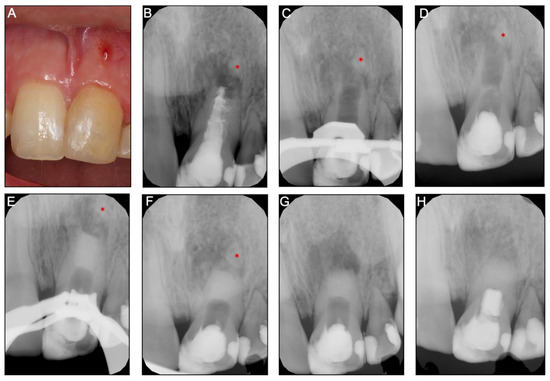

An 11-year-old girl was referred for REP of tooth 15. Her medical history was noncontributory. Sensibility tests (heat, cold, and electrical pulp testing) of the tooth 15 were negative, with evidence of coronal restoration leakage. Clinical examination showed that tooth 15 had edema and suppuration with sinus tract (chronic apical abscess), pain with vertical and lateral percussion, no mobility and the probing depth was within normal limits. Radiographically, the root canal was wide with a divergent open apical foramen (Figure 1A). After assessing the possibility of restoring the tooth without intracanal post and explaining all therapeutic alternatives to the patient and guardians, informed consent was obtained, and REP was performed. Local anesthesia was achieved with 3% mepivacaine (Mepivastesin®, 3M ESPE, Neuss, Germany). After isolation with a rubber dam, restorative material and carious lesions were removed and the access cavity was performed. After access, the wide-open canal was observed by dental microscope (Leica M320 F12, Leica Microsystems, Heerbrugg Switzerland) with 10x magnification depicting that some vital pulp tissue remained inside the root canal. The working length to this vital tissue was confirmed with paper points (size #80, Dentsply-Maillefer, Balaigues, Switzerland) by the presence of bleeding at 15 millimeters (mm). The canal was irrigated with 20 mL of 3% sodium hypochlorite (NaOCl; CanalProTM 3%, Coltène/Whaledent, Langenau, Germany) using a NavitipTM needle (Ultradent Products Inc, South Jordan, UT) at 13 mm, followed by rinsing with 20 mL of a saline solution for 5 minutes (min). The canal was dried with paper points, and intracanal medication of 45% calcium hydroxide (Calcicur Voco, Cuxhaven, Germany) (CH) paste was placed into the canal. The access cavity was sealed with a sterilized cotton pellet and CavitTM (3M, Neuss, Germany) and intermediate restorative material (IRM®, DentsplyDetrey GmgH, Konstanz, Germany). The patient was scheduled for a second visit after 4 weeks.

The tooth (15) was asymptomatic during the entire postoperative period, with no sinus tract or edema, and the temporary filling was intact. In the second session, local anesthesia was accomplished with 3% mepivacaine (Mepivastesin®, 3M ESPE, Neuss, Germany). Under the rubber dam, temporary material and cotton pellet were removed from the access cavity and the canal was rinsed with 20 mL of EDTA 17% (Coltène/Whaledent, Langenau, Germany) for 5 min, followed by irrigation with 5 mL of a sterile saline solution. The root canal space was dried with paper points and a microsurgical suction tip (Roeko Surgitip-endo, Coltène/Whaledent, Langenau, Germany). Subsequently, a manual sterilized k-file (size #25, Dentsply-Maillefer, Balaigues, Switzerland) was introduced until reaching the 15 mm working length and then deliberately pushed 2 mm past the working length to induce bleeding into the canal. After blood filled the canal up to 2 mm bellow cementoenamel junction (CEJ), an absorbable hemostatic gelatin matrix (Spongostan DentalTM, MS0005, Ethicon Inc, New Jersey, EUA) was placed over the blood clot. Finally, a 3 mm mineral trioxide aggregate barrier (ProRoot® MTA, Dentsply Tulsa Dental, Johnson City, TN, USA) was placed in the cervical third of the root canal with a coronal barrier (Buchanan Hand Barrierger #2; SybronEndo, Orange, CA, USA) over the blood clot. After placing a moist cotton pellet over the MTA, the access cavity was sealed with a temporary restoration material (CavitTM) and two weeks later replaced with a resin-based composite (SDRTM flow and Spectrum®, DentsplyDetrey GmgH, Konstanz, Germany).

After REPs, the tooth (15) was asymptomatic without signs of coronal discoloration. Follow-up was successively performed at 3, 6, 12 months, 3 years, and 5 years (Figure 1E,F and Figure 2). The radiographic evaluation depicted a continuity of the periodontal ligament space (confirming the absence of an apical radiolucency) as well as an appreciable increase in the root length and thickness. With the progression in time of follow-up, the partial separation of the apical root portion observed at 3, 6, and 12 months decreased significantly compared to the 2- and 5-year follow-up X-rays. After 5 years, a fully developed root structure was observed at the periapical radiography, and on the cone-beam computed tomographic (CBCT) scan (Supplementary materials: Video S1A, S1B), with an increase in length and thickness of the root walls as well as a decrease of the root canal lumen width.

Figure 1. Case report 1 with radiographic images of teeth 15: (A) preoperative periapical radiograph of tooth indicating the root canal was wide with a divergent open apical foramen, the existence of periapical lesion and thin root dentinal walls; (B) radiograph of the tooth after chemomechanical debridement with 3% of NaOCl irrigation and calcium hydroxide application; (C) after 4 weeks, the cervical barrier with 4 mm of MTA; (D) final restoration with direct composite resin restoration; (E) 3-month follow-up periapical radiograph; (F) after six months of following, the radiograph shows periapical healing as well as mesial and apical root formation with larger dentinal walls.